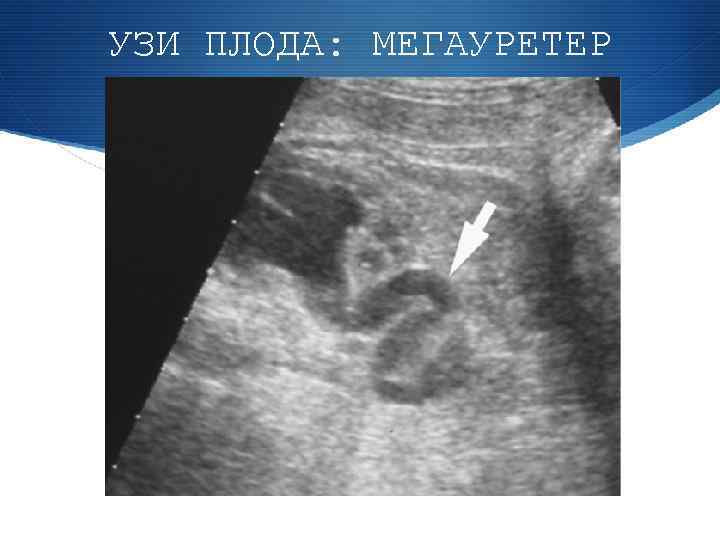

УЗИ ПЛОДА: МЕГАУРЕТЕР